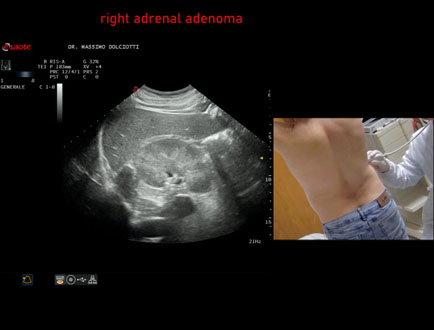

Data inserimento: 06/11/2025

Ecografia del: 31/10/2025

Strumento: Esaote MyLab Eight

Sonda: Convex Multifrequenza 1-8 MHz

Età Paziente: F 69 anni

Motivazione dell'esame: follow up per piccolo adenoma surrenalico.

Commento all'esame: le immagini ed il video documentano in sede surrenalica destra, formazione ipoecogena, a margini definiti, rotondeggiante, delle dimensioni di 15,8 x 14,8 mm, da ricondurre ad adenoma surrenalico.

Conclusioni: piccolo adenoma surrenalico destro (small right adrenal adenoma).

Presentazione: Dr. Massimo Dolciotti - Ancona